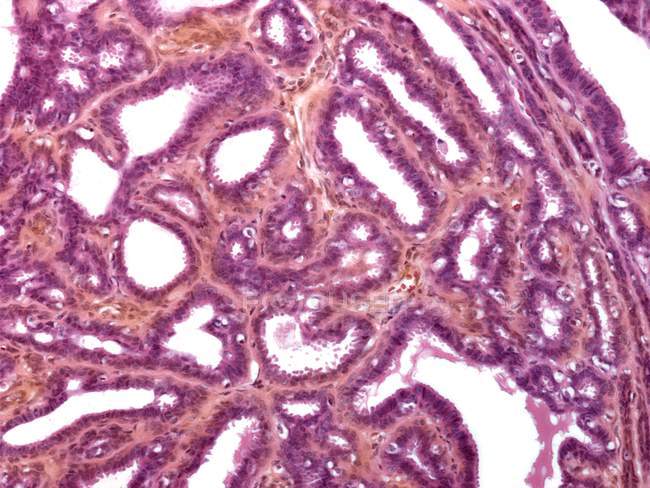

Исследование: микропрепарат молочной железы в медицине

Раздел: Снимки-откровения